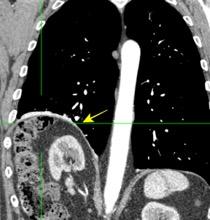

T. mixto de células germinales del testículo izquierdo

Nódulos pulmonares múltiples. (flechas verdes). Masas paratraqueales. (flechas amarillas). Dudoso ensanchamiento retrocrural (flechas negras). sigue….

Ttawfik A et al. Trans-diaphragmatic Pathologies: Anatomical Background and Spread of Disease on cross-sectional Imaging. Current Problems in Diagnostic Radiology. 2021.

T. mixto de células germinales del testículo

izquierdo Metástasis pulmonares. (flechas verdes). Ganglios paratraqueales. (flechas amarillas). Ganglios retroperitoneales (flechas negras)

Tawfik A et al. Trans-diaphragmatic Pathologies: Anatomical Background and Spread of Disease on cross-sectional Imaging. Current Problems in Diagnostic Radiology. 2021.